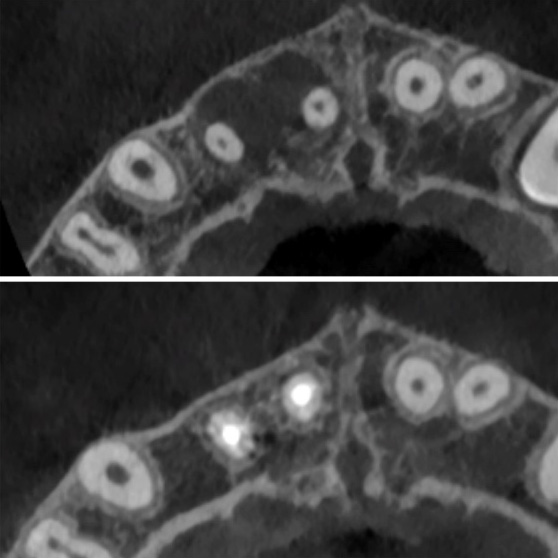

Initial CBCT IMAGES showing the complete healing of the lesion

2 years follow up CBCT IMAGES showing the complete healing of the lesion